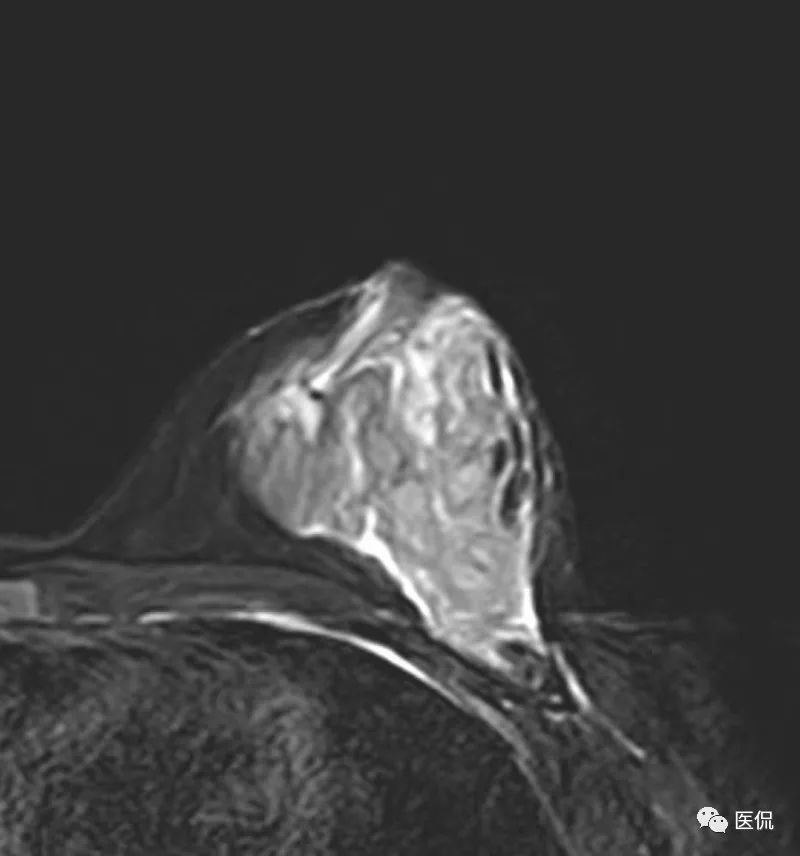

MRI检查设备为PHILIPS Achieva 3.0T超导型MRI扫描机,专用乳腺8通道相控阵线圈。患者俯卧位,双乳自然悬垂。先行横轴位梯度回波T1WI序列(TR/ TE=5.15/2.59ms),横轴位快速自旋回波脂肪抑制T2WI序列(TR/ TE=7989.15/70.00ms)平扫,FOV=35cm×16cm,层厚4mm,层间距0.4mm。后行横轴位、矢状位DCE-MRI扫描,采用三维容积梯度回波成像技术脂肪抑制序列(TR/TE=5.4/2.7ms),造影剂用量14ml,速率2ml/s,设定8个时相,无间断扫描,每个时相扫描时间为111s,总动态增强时间约14.8min,FOV=35cm×16cm,层厚4mm,层间距0.4mm。DWI序列,b值0,600。

该例患者有先天性乳头凹陷, MRI图像上,病灶范围较广泛,呈片状,边缘不清,累及乳后间隙,增强后不均质强化,时间信号曲线为平台型,应首先考虑为炎性病变。

本病例特点为年轻女性,以发现左乳肿块1+月就诊,病程较短,有先天性乳头内陷。X钼靶显示左乳外下象限腺体结构紊乱,密度增高,边缘模糊,无钙化,腋窝无增大淋巴结。超声显示病灶范围较为广泛,为混杂低回声区,边缘不清。MRI显示病灶呈片状稍长T2信号,边缘不清,DWI(b=600)为稍高信号,增强后明显不均质强化,时间-信号曲线为平台型。上述影像表现均提示病变范围广泛,边界模糊不清,无肿块显示,结合患者先天性左乳头凹陷,有乳腺炎发病基础,因此在诊断上首先需要考虑浆细胞性乳腺炎的可能性。

乳腺X线摄影是基本检查方法,主要表现为患侧乳腺的大片密度增高,边缘不清,有时可在病灶区域内看到迂曲透亮的扩张导管影。超声可清晰显示扩张的导管,浆细胞性乳腺炎一般分为三型:(1)包块型,肿块多位于乳晕附近,边界不清,形态不规则,与乳腺癌不易鉴别;(2)单纯导管扩张型:乳腺腺体内见多发扩张导管,内透声差;(3)脓肿形成型:范围较广泛,边界模糊,脓肿形成后深压探头可显示脓液流动,光点漂浮。MRI检查具有较好的组织分辨率及空间分辨率,能从多个角度显示病灶的信号、形态特点,T1WI呈等低信号,压脂T2WI呈高信号,动态增强呈不均匀明显强化,脓肿形成后脓肿壁环形强化,DWI脓腔呈明显高信号,时间-信号强度曲线多为I型或II型。对与乳腺癌鉴别具有较大意义。